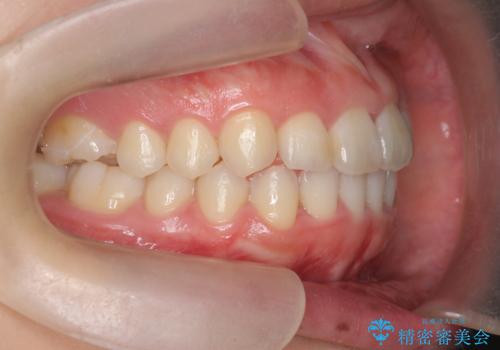

前歯の見た目を改善したい

- ねじれの目立つ前歯の見た目を改善したいと矯正治療を希望され来院されました。

がたつきの改善をマウスピース矯正インビザラインで行っていきます。

ガタつきの改善はもちろん、歯列全体のアーチも放物線状にきれいに排列し審美性を向上させることができました。